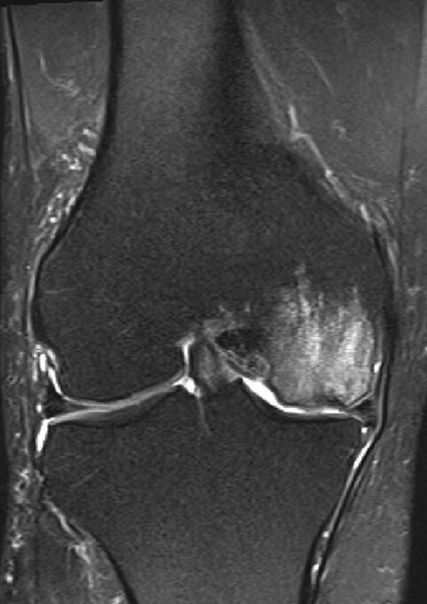

Ein 62-jähriger Patient stellte sich im März 2025 mit belastungsabhängigen Knieschmerzen rechts vor. Im MRT zeigte sich eine Läsion des medialen Meniskus, sodass in Zusammenschau mit dem positiven Meniskuszeichen in der klinischen Untersuchung eine partielle Meniskektomie durchgeführt wurde. Die postoperative Phase verlief zunächst unauffällig. Der Patient berichtete über ein beschwerdefreies Intervall von rund sieben Wochen. Anschließend entwickelten sich jedoch erneut zunehmende Schmerzen im rechten Kniegelenk, die eine erneute Vorstellung in der Spezialambulanz erforderlich machten. Er berichtete vor allem über belastungsabhängige Schmerzen im Bereich des medialen Kniegelenks. Daraufhin wurde ein Ganzbeinröntgen zur Beurteilung der Beinachse durchgeführt, hier zeigte sich eine varische Beinachse mit 5 Grad Varus (Abb.1). In der ergänzend durchgeführten MRT-Untersuchung konnte medialseitig eine ausgeprägte Nekrosezone am medialen Femurkondyl nachgewiesen werden (Abb.2). Schlussendlich wurde aufgrund dieses Befundes die Indikation zur Implantation einer medialen Hemischlittenprothese rechts gestellt, die schließlich im August 2025 komplikationslos durchgeführt wurde (Abb.3+4).